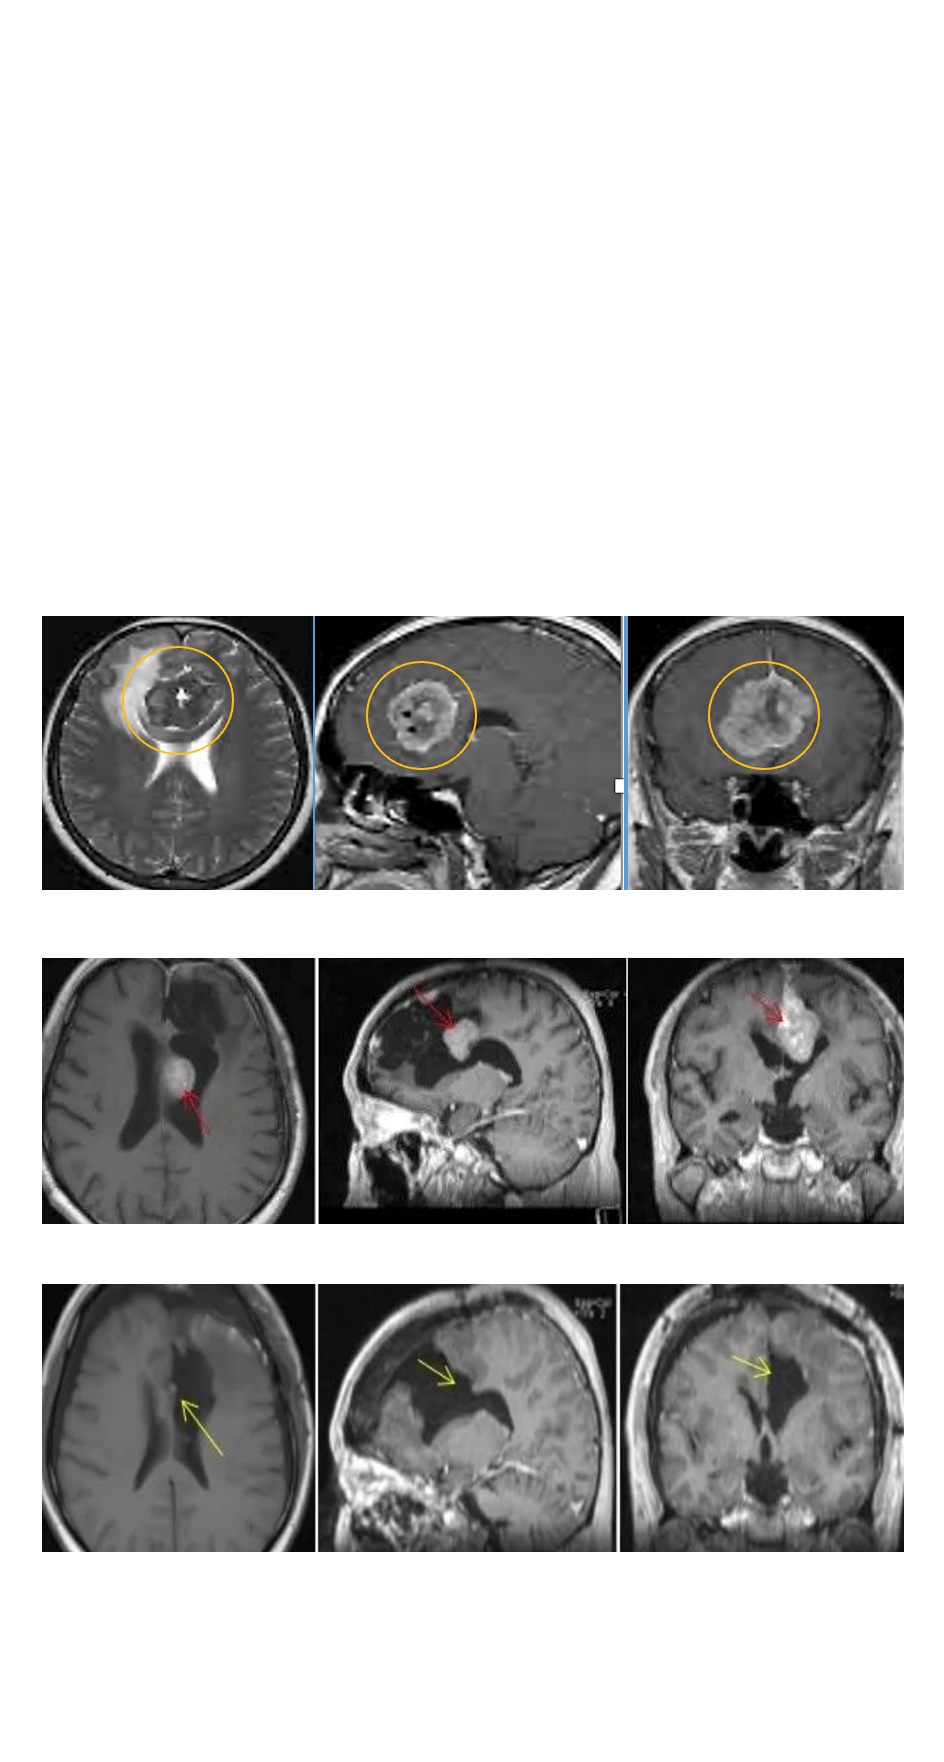

没想到二年复查后就出现脑膜瘤复发的情况,于是又在专家建议下进行伽玛刀治疗。然而,3年后的治疗结果更是让全家人陷入绝望:MRI影像显示大脑镰前段基本均受累,并有大脑镰右侧肿瘤生长,矢状窦被累及,左侧额部凸面硬脑膜多处肿瘤生长。这代表病情进一步恶化成了多发脑膜瘤。

图片

在术中iMRI、术中神经导航等国内少有的高科技复杂仪器辅助下,INC德国巴特朗菲教授为赵先生实施了手术,大脑镰旁及矢状窦旁的肿瘤被完全切除,并地保护了正常的脑组织结构,展现了其国际水准的技术水平和教授风采。